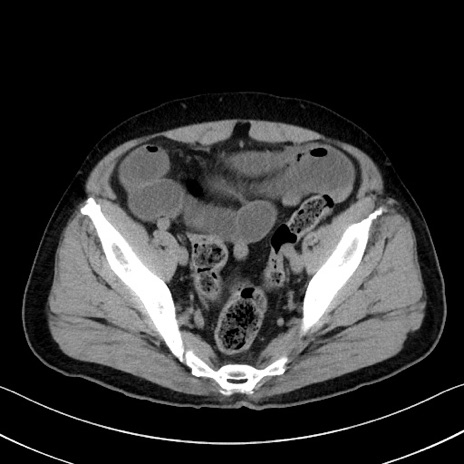

冠状断像